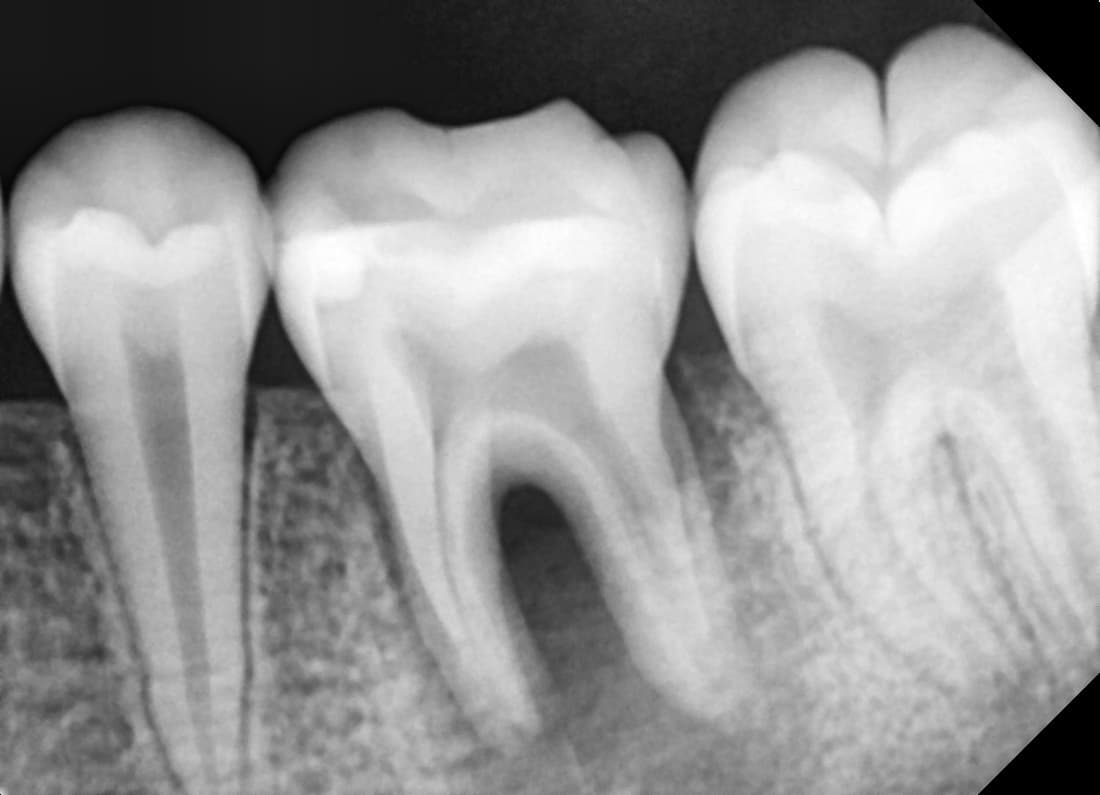

치근단병소 치유

심한 염증으로 고름이 찬 어금니

Before

After

치료 6개월 후 치근단병소 완전 치유